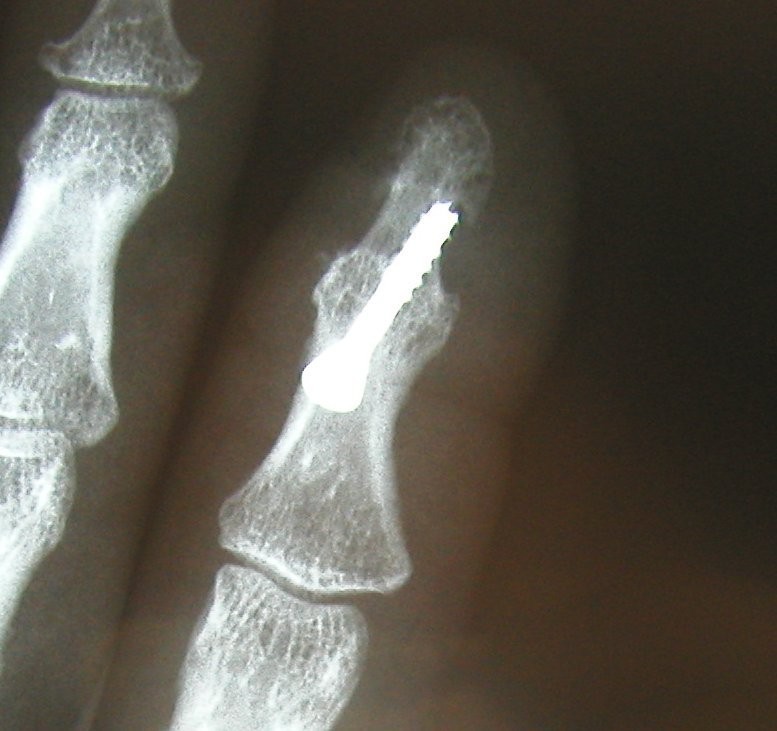

Middle and right: stiffening in the functional position with the V-tek regular screw. Eliminates pain and visually shows a satisfying result.

Below: End-joint stiffening in the index finger and middle-joint endoprosthesis in the middle finger